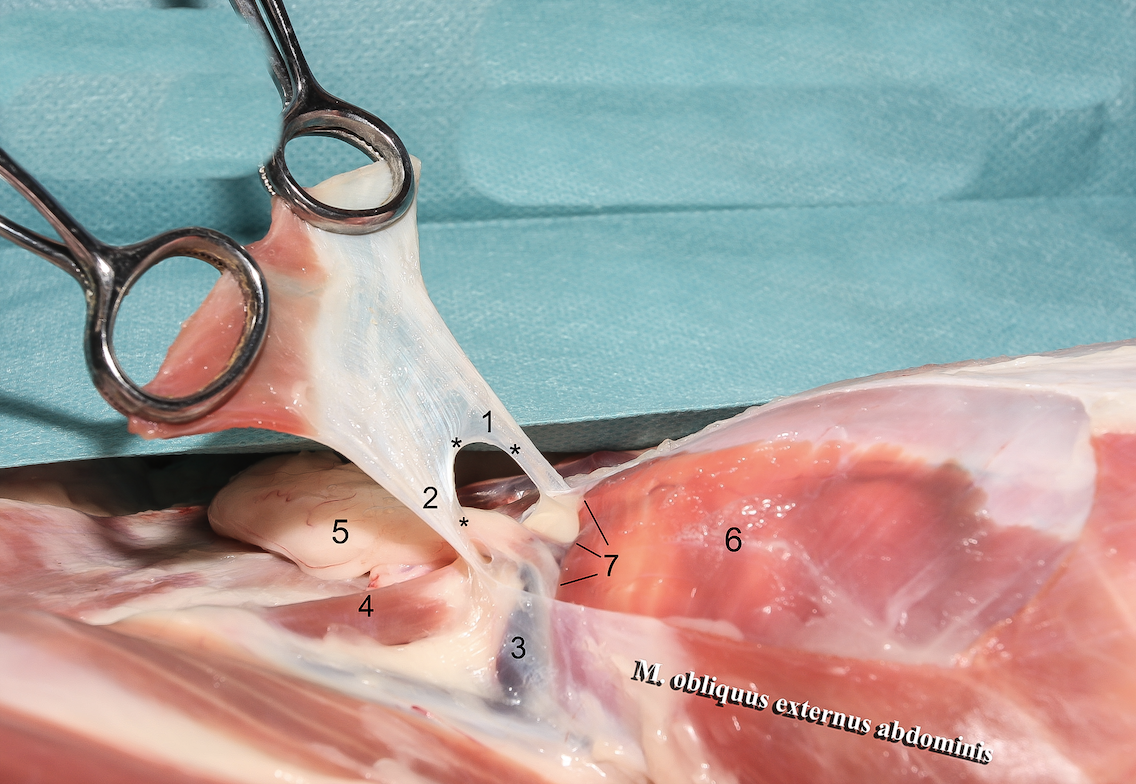

1

A

Crus mediale

6

Q

2

A

Crus laterale

7

Q

3

A

A./v. pudenda externa

8

Q

4

A

A./v. femoralis

9

Q

5

A

Processus vaginalis

10

Q

6

A

A./v. pudenda externa